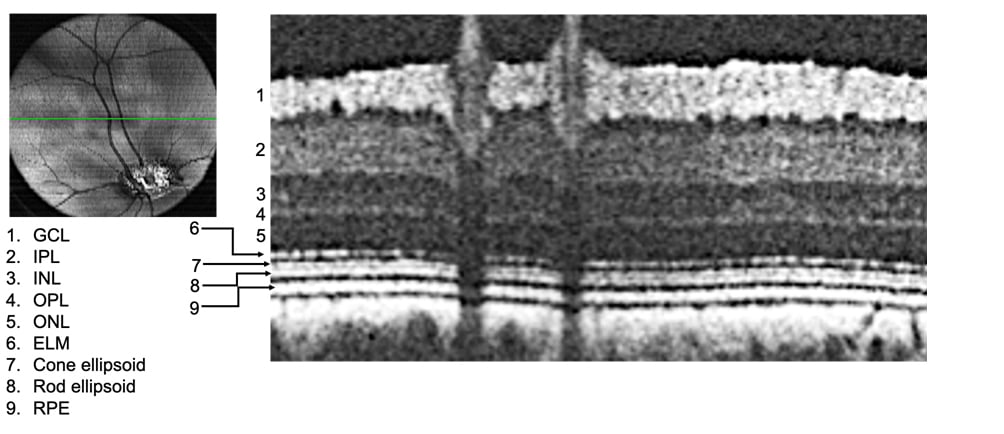

Figure:

Left: A Fundus image of a pig eye showing the retina and blood vessels. Right: A cross section of the region of the fundus denoted by the green line shows the different retinal layers. GCL: ganglion cell layer; IPL: inner plexiform layer; INL: inner nuclear layer; OPL: outer plexiform layer; ONL: outer nuclear layer; ELM: external limiting membrane; RPE: retinal pigmented epithelium. The layered architecture is similar to that of a human retina. (Imaged by Dr. Bhubanananda Sahu, Research Specialist, Department of Ophthalmology & Visual Sciences, UMMS).